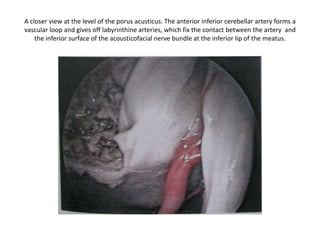

A closer view at the level of the porus acusticus. The anterior inferior cerebellar artery forms a

vascular loop and gives off labyrinthine arteries, which fix the contact between the artery and

the inferior surface of the acousticofacial nerve bundle at the inferior lip of the meatus.